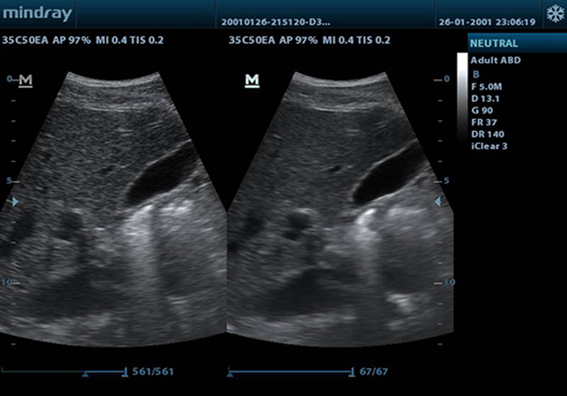

Power

Power Doppler membantu mengidentifikasi aliran darah dalam kondisi klinis yang berbeda, yang penting untuk membantu menetapkan lokasi pembuluh darah, mempermudah pengukuran secara akurat.

PW

PW Doppler dan Pelacakan Otomatis menampilkan detail aliran darah untuk diagnosis yang bersifat lebih komprehensif.